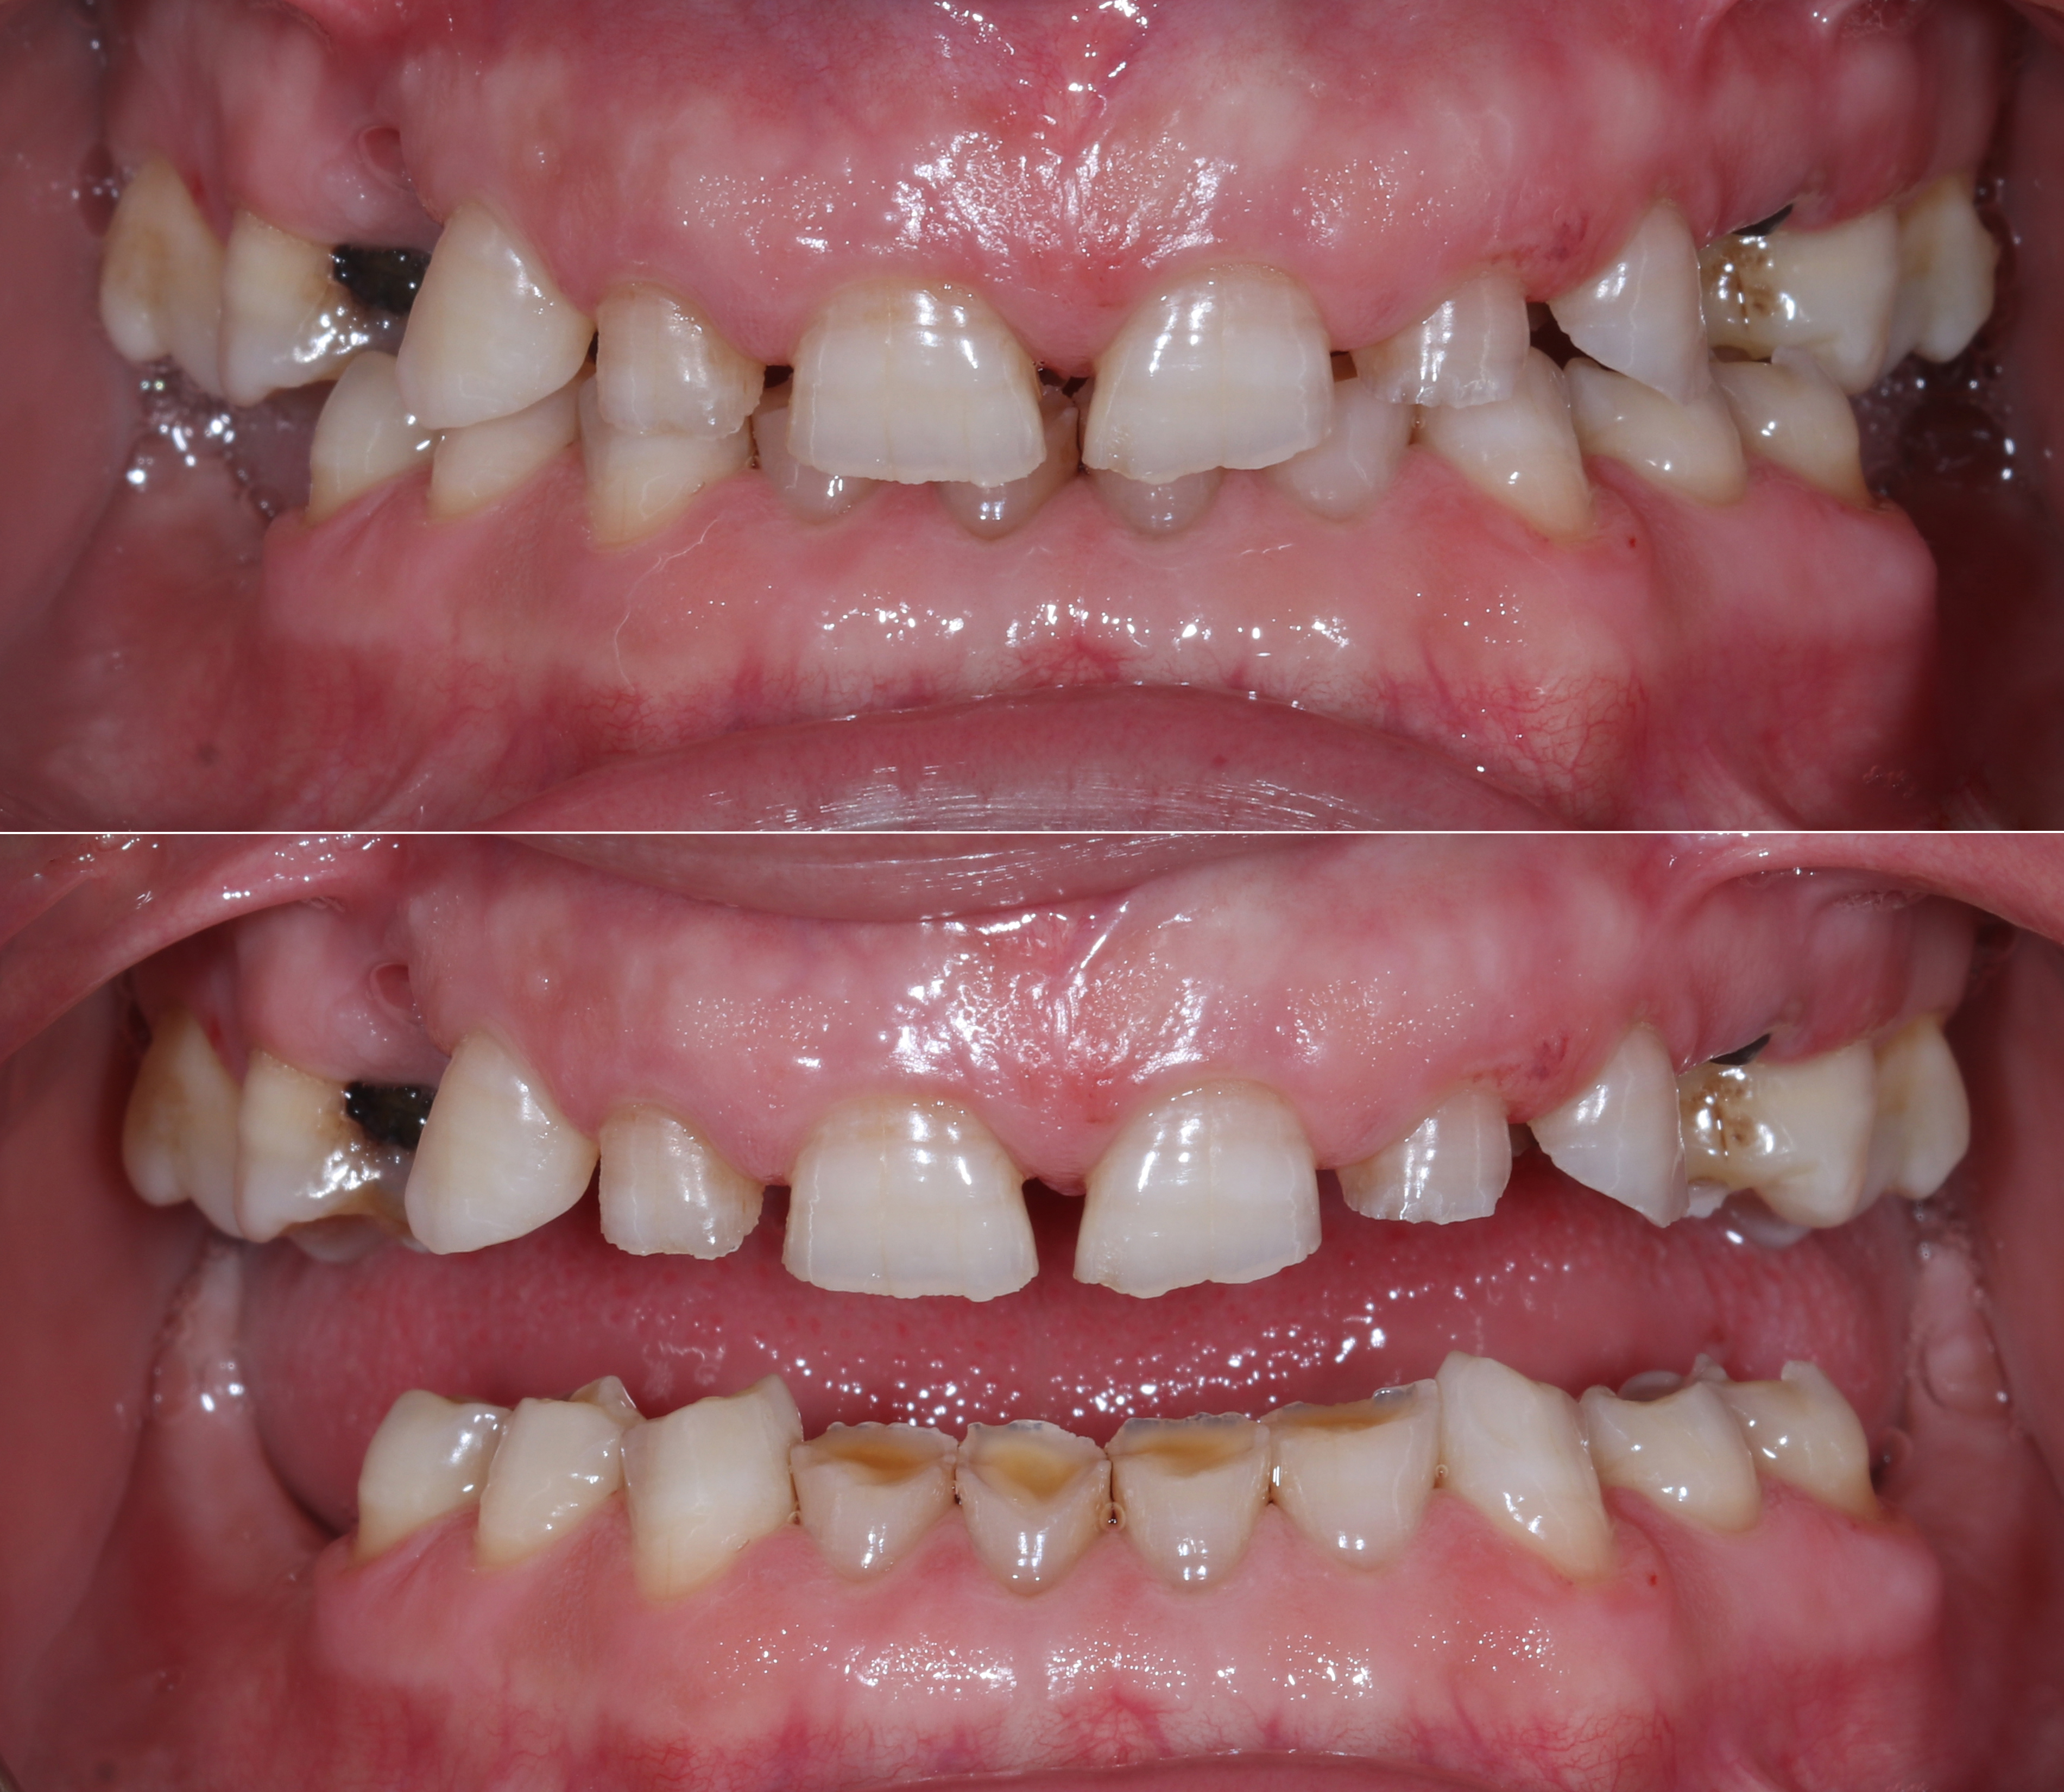

Ασθενής με αποδιοργανωμένη, εκτενώς φθαρμένη οδοντοφυΐα, τερηδόνες και κατεστραμμένα δόντια στην άνω γνάθο που προκαλούσαν έντονους πόνους, προσήλθε στο Aesthetic Dental Studio στην Καλαμάτα με στόχο την αισθητική και λειτουργική αποκατάσταση του στόματός της.

Σε πρώτη φάση, αφαιρέθηκαν τα δόντια που ήταν πλήρως κατεστραμμένα, πραγματοποιήθηκαν ενδοδοντικές θεραπείες στα δόντια που μπορούσαν να αποκατασταθούν και έγιναν εμφράξεις σε δόντια με απλή τερηδόνα. Έτσι, το στόμα σταθεροποιήθηκε και ήταν πλέον έτοιμο για την δεύτερη φάση της θεραπείας, που περιελάμβανε την προσθετική αποκατάσταση των δοντιών.

Στην συνέχεια, κατασκευάστηκαν προσωρινές ακρυλικές αποκαταστάσεις καθ' εικόνα και ομοίωση του διαγνωστικού κερώματος ώστε τα παραπάνω να εξετασθούν και στην πράξη στο στόμα της ασθενούς.